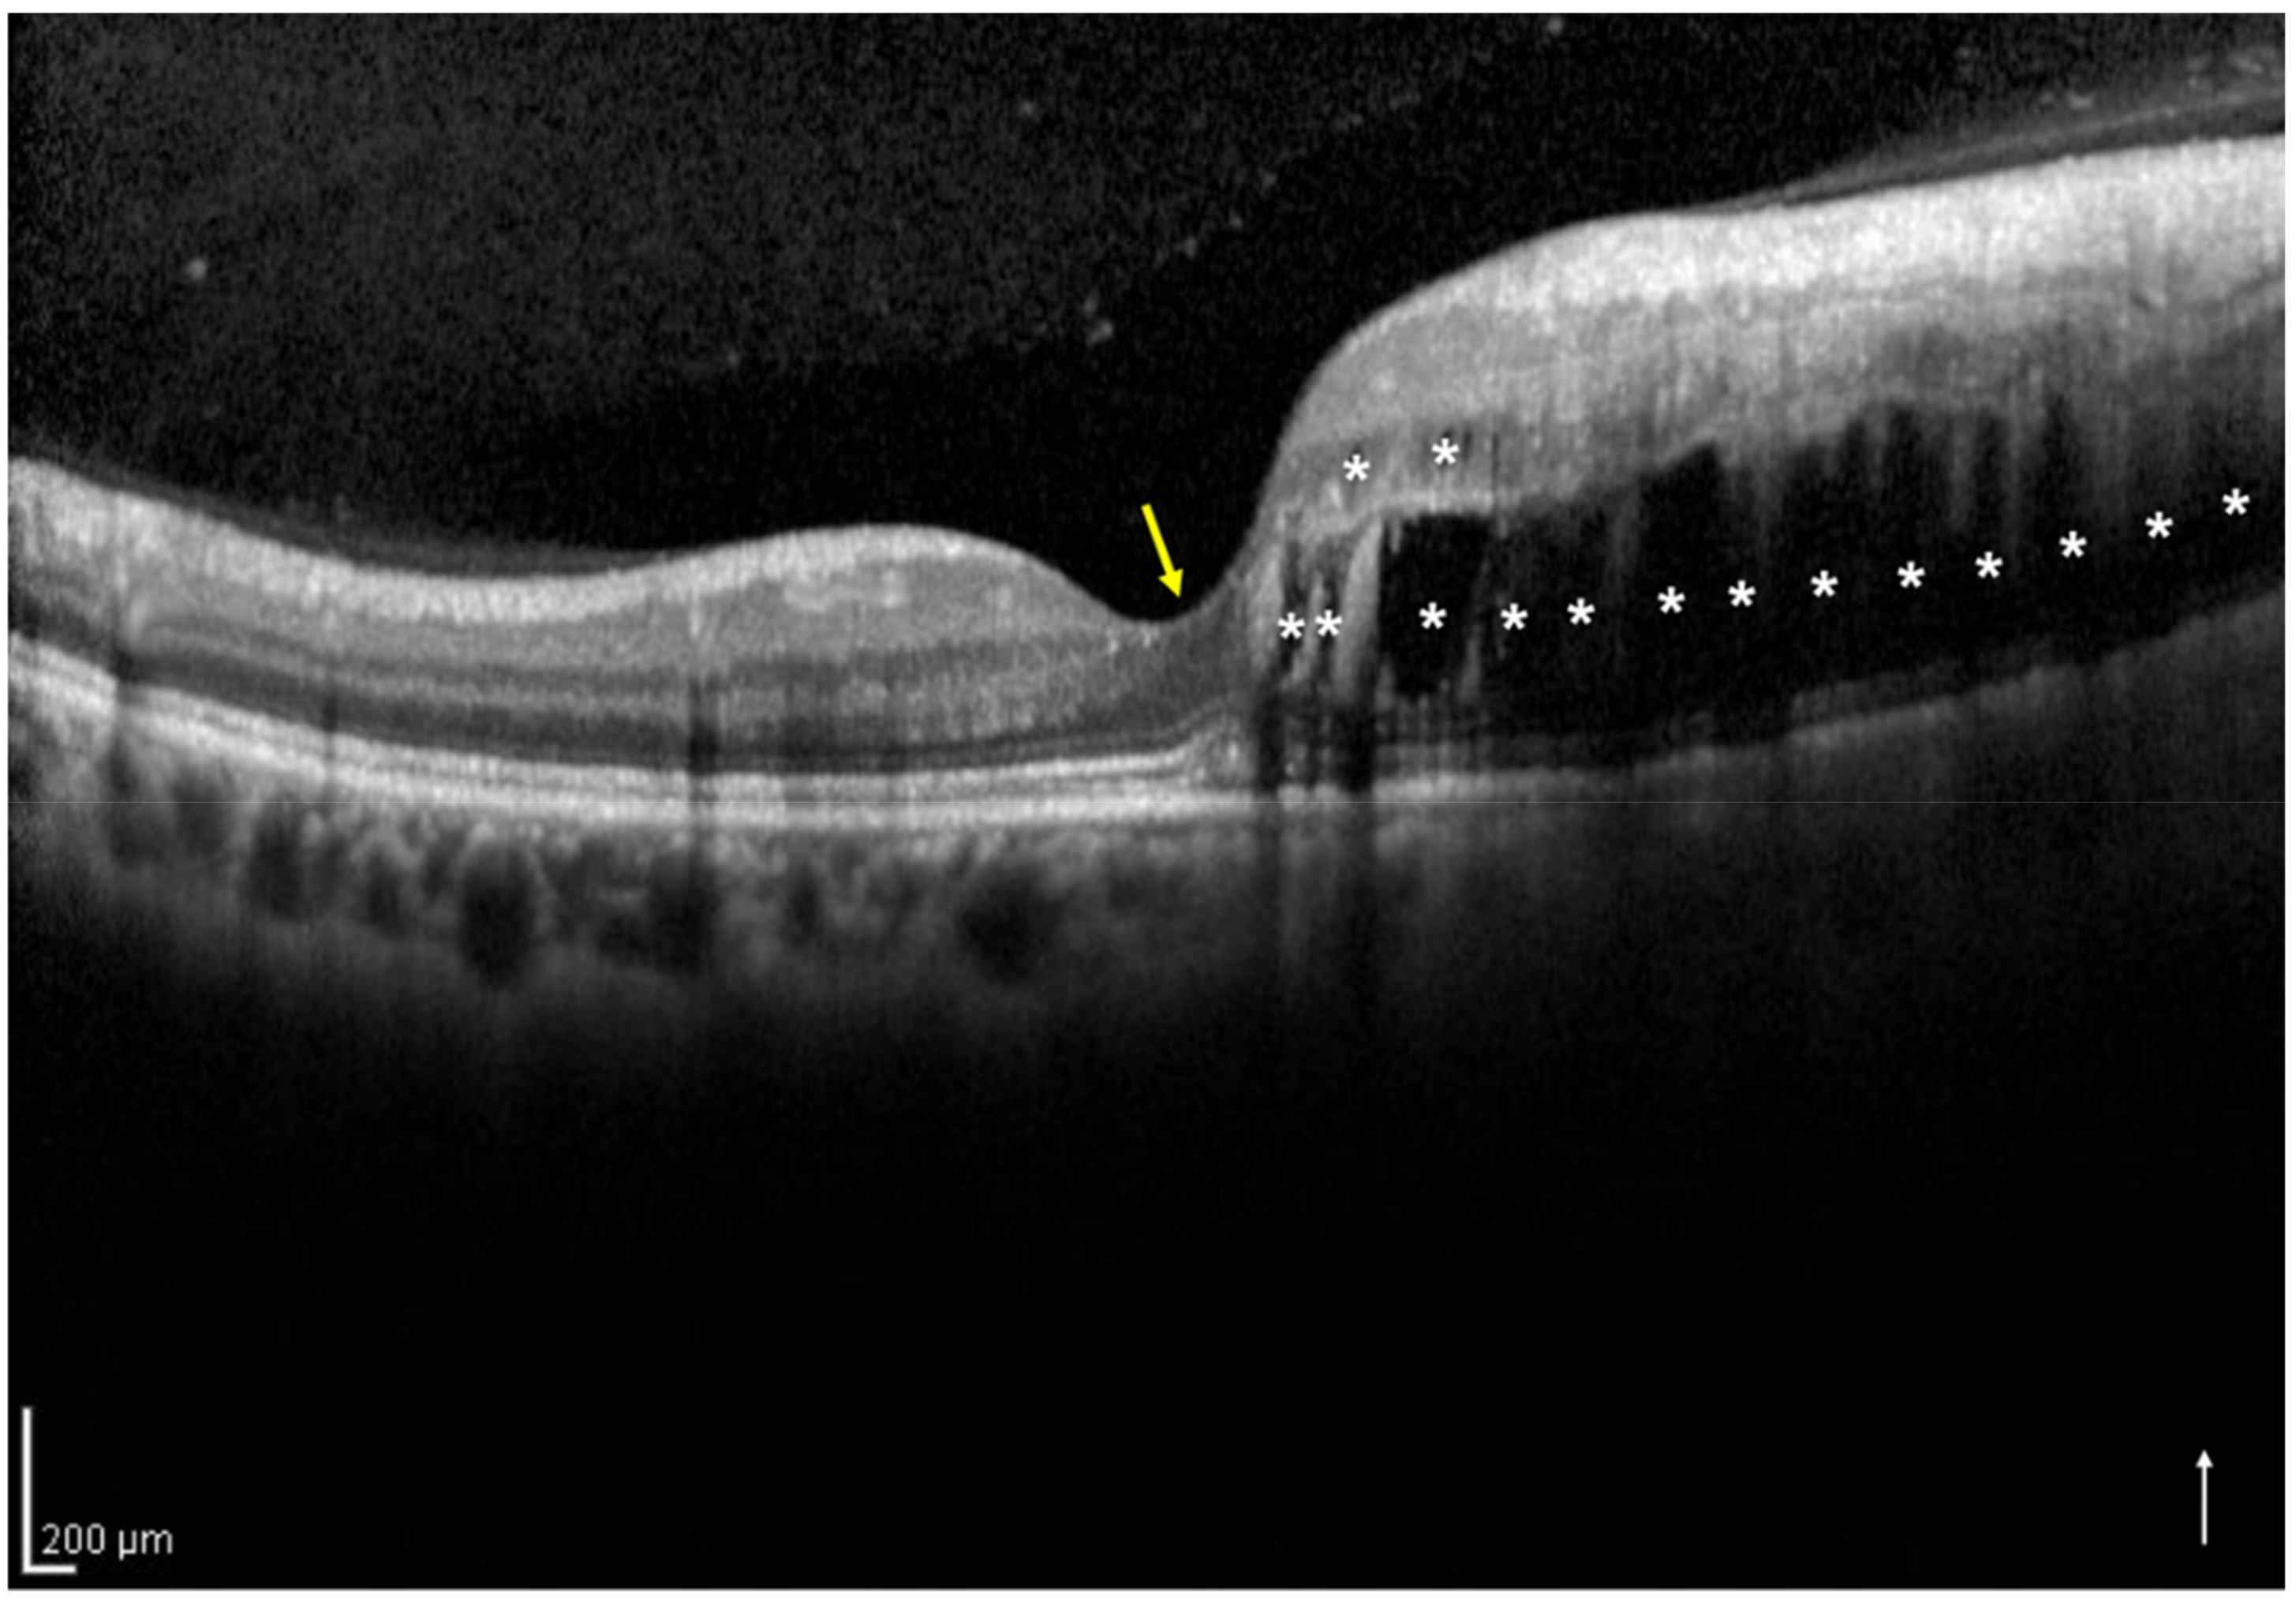

2.3. Definition and Classification of the Two Groups Using Optical Coherence Tomography

| No. of eyes with one-side IRF/both-sides IRF | 33/17 | |